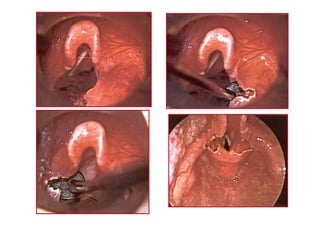

KORDOPEKSKORDOPEKS

VFVF üüst yst yüüzeyindenzeyinden

gegeççen ien i ne ucune ucu

VF alt yVF alt yüüzeyindenzeyinden

2/02/0 polipropilenpolipropilen